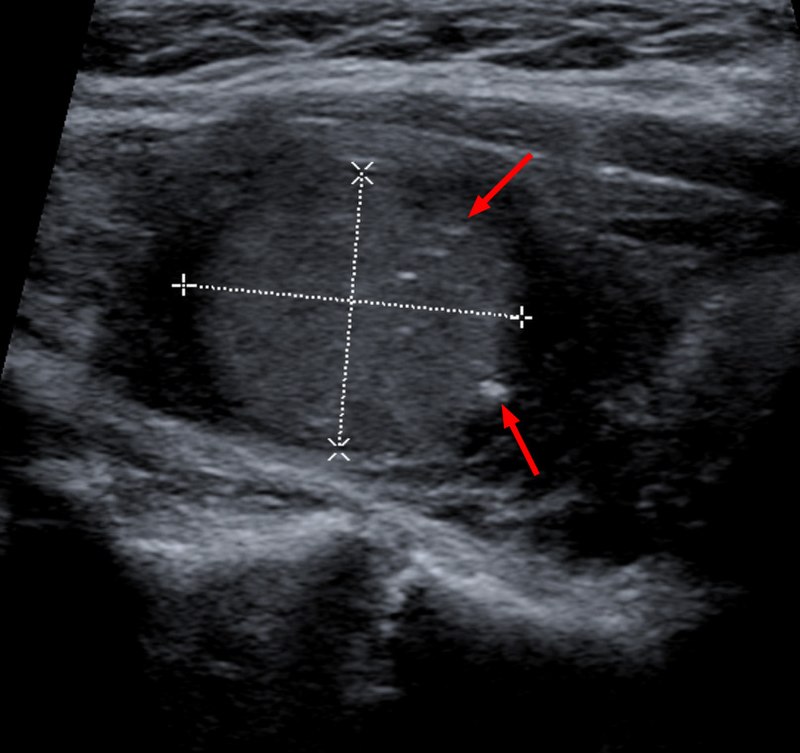

Thyroid nodules are more likely to be benign than malignant, and thyroid neoplasia usually appears as a distinct, solitary nodule.

I-131 radioactive uptake studies are useful to further characterize nodules.

Increased uptake (hot nodule) is seen in Graves’ disease or nodular goiter.

Decreased uptake (cold nodule) is seen in adenoma and carcinoma and they often warrant biopsy.

Biopsy is performed by fine needle aspiration (FNA).